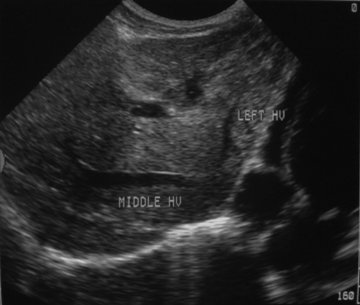

Hasil Penelitian : Sonografi Sirosis Hepatis di RSUD Dr. Moewardi

Suyono, Sofiana, Heru, Novianto, Riza, Musrifah (Bagian Radiologi Fakultas Kedokteran Universitas Sebelas Maret/Rumah Sakit Umum Daerah Dr. Moewardi Surakarta). Cermin Dunia Kedokteran , No. 150, 2006PENDAHULUANPenyakit hepar terutama hepatitis yang disebabkan oleh virus (terutama virus hepatitis B) saat ini sedang melanda dunia baik di negara maju maupun negara berkembang. Munculnya virus baru yaitu virus Hepatitis…